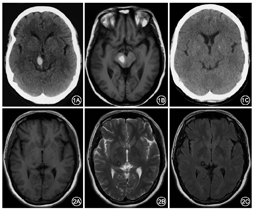

所有患者均存在颅内器质性病变,中脑(15例)、丘脑(11例)及小脑(7例)依次为常见的病变部位(注:多发病变者部位有重叠,故病变总数>23)。分组显示:孤立病变组12例(52.2%)、多发病变组11例(47.8%);中脑受累组15例(65.2%)、非中脑受累组8例(34.8%)。孤立病变组与多发病变组TRS总分比较差异无统计学意义[(47±17)分比(50±14)分,P=0.57];而中脑受累组与非中脑受累组TRS总分比较差异有统计学意义[(58±14)分比(38±11)分,P=0.00]。典型病例:例1中脑右侧出血(图1),震颤却波及四肢及头部(TRS总分84分);例2右侧丘脑海绵状血管瘤(图2),震颤仅局限于左侧肢体(TRS总分42分)。

本研究显示HT的震颤既可为单侧(14例,60.9%),亦可双侧(8例,34.8%),其中例1中脑右侧出血导致四肢及头部震颤,且病灶同侧肢体震颤更重,既往文献未见类似的报道,其确切机制不详。HT的发病机制非常复杂,目前认为黑质-纹状体多巴胺能系统、小脑-丘脑-皮质环路以及齿状核-红核-橄榄核环路均可能参与其中[5,10],结合该患者既往有左侧小脑出血病史,根据Brittain等[11]报道小脑梗死患者所出现的同侧的HT,推测该病例可能与新发中脑病变导致小脑齿状核-红核-橄榄核环路的失交联有关。

既往报道导致HT的病变部位包括中脑、桥脑、延髓、丘脑、小脑等[3,4,5,11],目前最大宗的病例报告发现易受累部位依次为中脑、丘脑与小脑,占全部受累部位的82.7%[3]。本研究亦显示中脑、丘脑及小脑是常见的原发受累部位。有关HT原发病变的影像学特征与临床症状之间的关系目前尚无定论。Raina等[3]的观察性研究提示震颤的临床严重程度与病灶的数目和范围无明显关联。本研究对孤立病变组和多发病变组的震颤严重程度进行比较后发现二者并无显著差异,进一步支持了上述观点。而本研究发现中脑受累患者的震颤明显重于非中脑受累者,提示中脑核团损害在HT的发病中起到重要作用,如病例1示因中脑出血继发了广泛而严重的震颤。总之,本研究首次考察了病变解剖部位与临床严重程度的关系,初步提示中脑受累或与HT症状的严重程度有一定关联,但仍需功能影像学研究证实并阐明其机制。